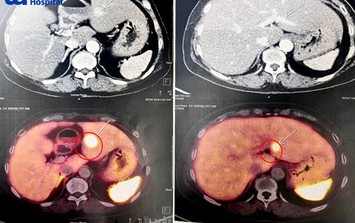

Mệt mỏi, sụt cân, người phụ nữ 65 tuổi đi khám phát hiện nổi u khắp người, tiến triển di căn gan

Bệnh thường gặpGĐXH - Điều đáng lo ngại nhất của người bệnh này là đa u tuyến nội tiết tiến triển đã di căn gan, tiên lượng còn rất dè dặt và cần theo dõi sát.